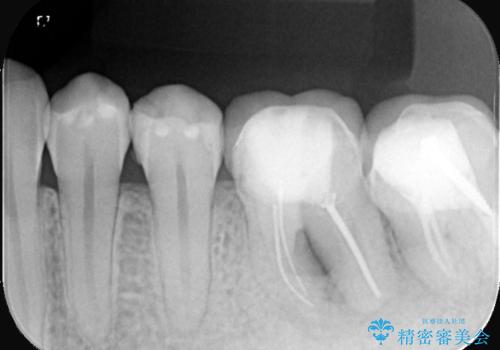

左下6番目の歯の周りに大きく透過像を認め、再根管治療後の予後が良くない可能性が大きく当院でも抜歯適用歯と説明しました。欠損部に対しインプラント治療や歯牙移植(左下の親知らずの移植)、ブリッジを提案し、歯牙移植を行うこととなりました。

保存が難しい左下6番目の歯を抜歯し、左下8番目の歯(親知らず)を抜歯窩に移植しました。歯牙移植後の動揺防止のため暫間固定を行っています。

また移植後2週間経過時点で根管処置が必要となります。